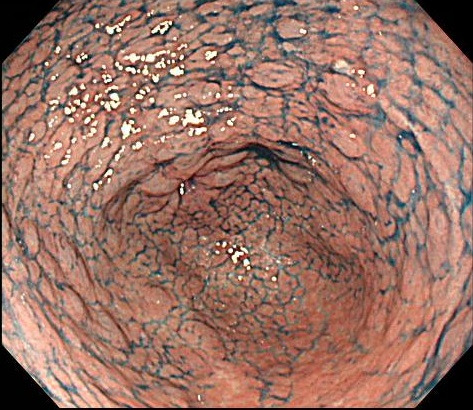

위축성 위염 및 장상피화생 평가

- 위점막의 얇아짐, 창백함

- 위산 분비 감소

- 장점막 형태가 나타나는 변화

이 두 가지 변화는 위암의 전구 병변으로 간주되기 때문에 정기적인 조직검사 추적이 중요합니다.